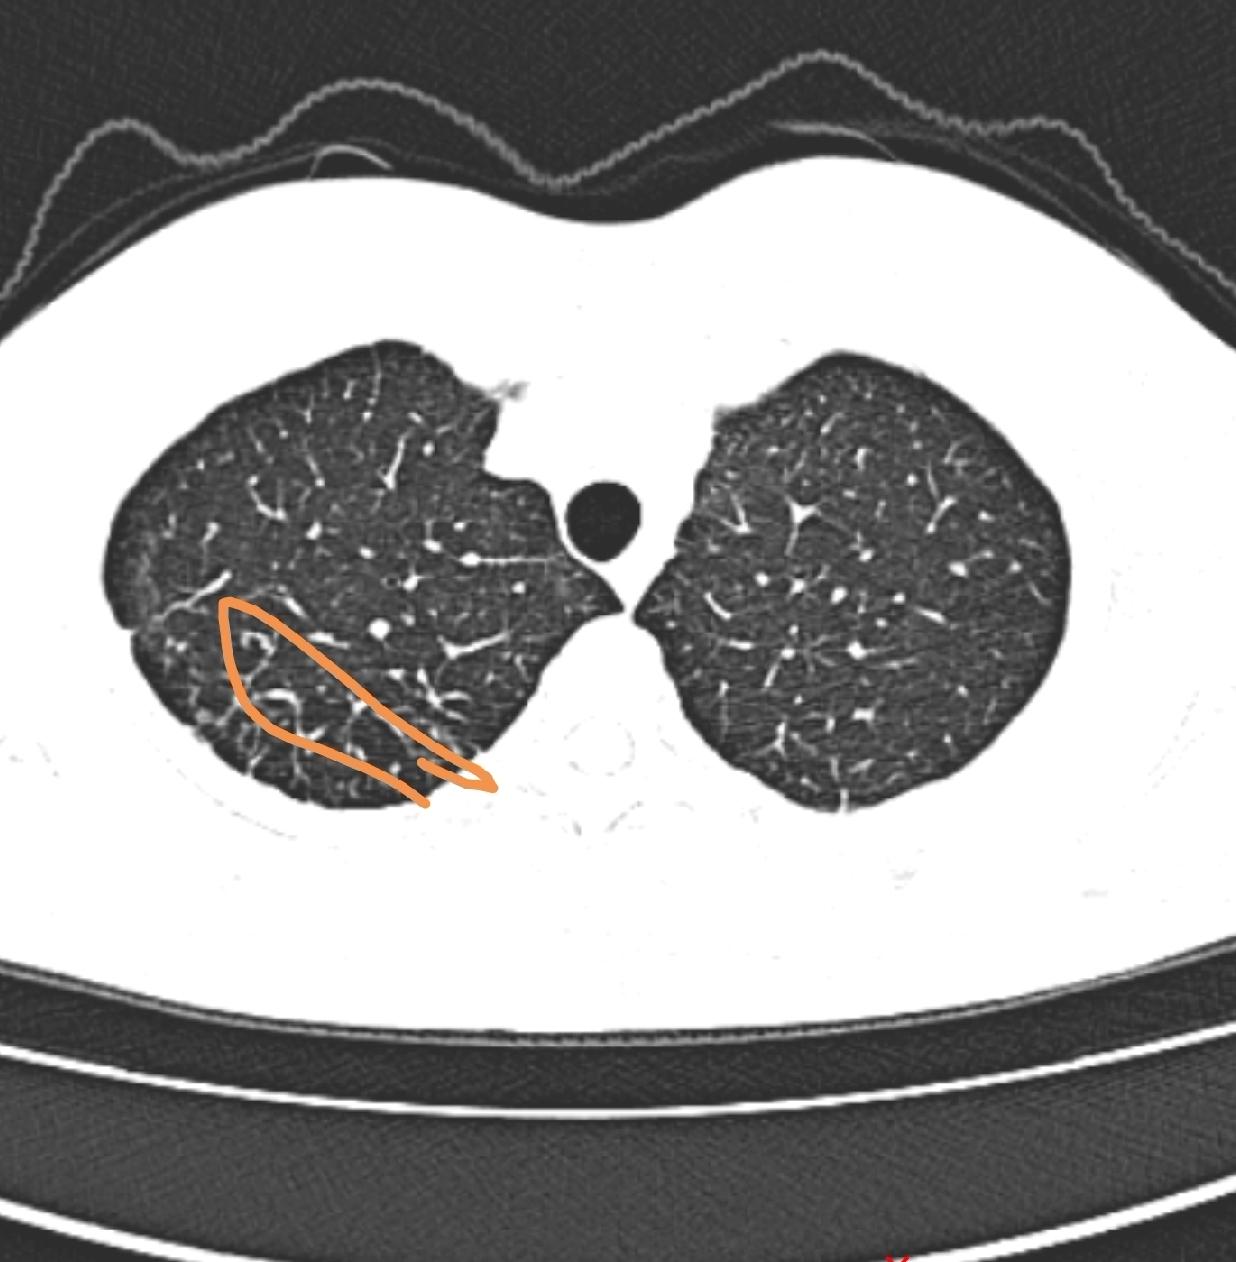

肺部结节有一部分是恶性的,这一小部分恶性结节导致每一个结节患者都很焦虑,肺结节如

肺部结节若为肺癌,会有这些“危险变化” 在临床诊疗中,肺部结节是呼吸科常见的“信

肺部结节多数是良性,为什么还有很多人害怕,问题出在少数当中 肺部结节是很多人的噩

肺部病灶为什么多数无法完全消掉,有些人肺CT报告上终生有慢性炎症 肺是一次性的器